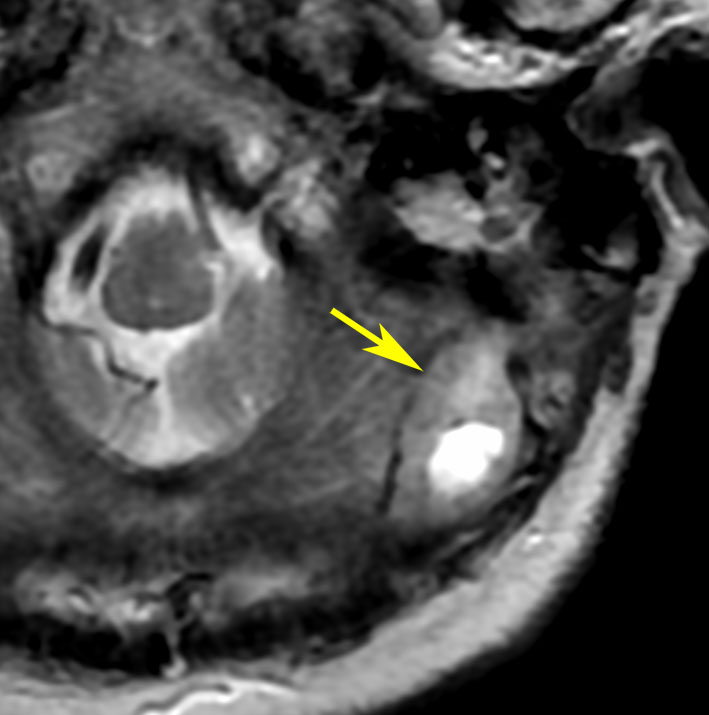

放射線治療によって誘発される2次癌としての ヘマンジオペリサイトーマ

1984年 19歳の時に,松果体のジャーミノーマに全脳照射45グレイで治療されました(左CT)。1997年左蝶形骨縁にヘマンジオペリサイトーマが発生しました(中央と右のMRI)。手術で全摘出しましたが4年後,2001年に脊髄に播種再発してつらい経過を辿りました。眼窩壁を破る典型的なヘマンジオペリサイトーマの像で,放射線誘発髄膜腫との鑑別がとても大切なものです。